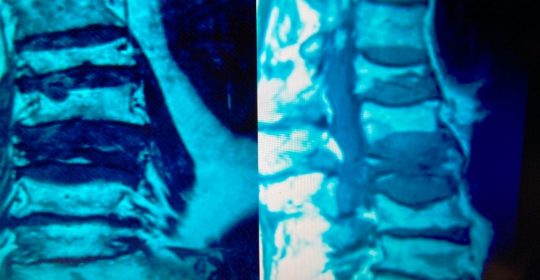

Εικόνα 5 α,β, :Μαγνητική Τομογραφία της Οσφυϊκής Μοίρας της Σπονδυλικής Στήλης. Προσθιοπισθία και πλαγία λήψη. Παρατηρείται καθίζηση λόγω οστεοπόρωσης των σωμάτων πολλών οσφυϊκών σπονδύλων

- α

- β